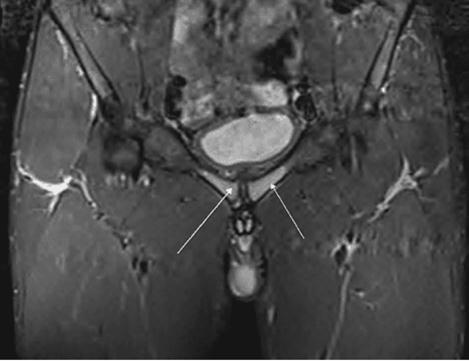

Issuu converts static files into: digital portfolios, online yearbooks, online catalogs, digital photo albums and more. Sign up and create your flipbook.